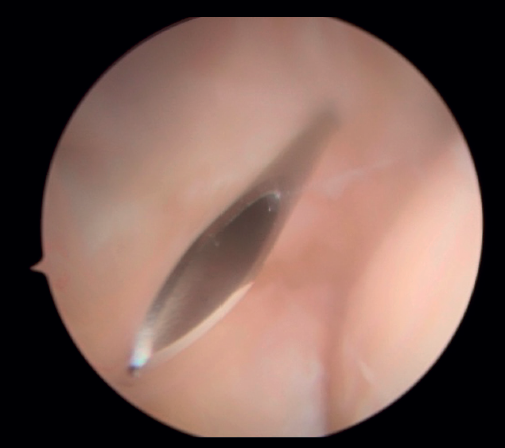

Posteriormente, se realiza la capsulotomía parcial lateral con sinoviotomo o vaporizador, hasta conseguir apreciar el ECRB (Figura 7). Una vez que se consigue su visualización, mediante el sinoviotomo y el vaporizador, se procede a la tenotomía de la inserción del ECRB en el epicóndilo, así como del tejido degenerativo tendinoso asociado (Figura 8). La liberación del tendón del ECRB debe limitarse a una zona anterior al eje central de la cabeza radial con el codo a 90°, para preservar la integridad del ligamento colateral lateral.

Figura 7. Tendón extensor carpi radialis brevis tras capsulotomía lateral (paciente en decúbito lateral, codo derecho, visión desde el portal medial).

Figura 8. Tenotomía del extensor carpi radialis brevis con vaporizador (paciente en decúbito lateral, codo derecho, visión desde el portal medial).